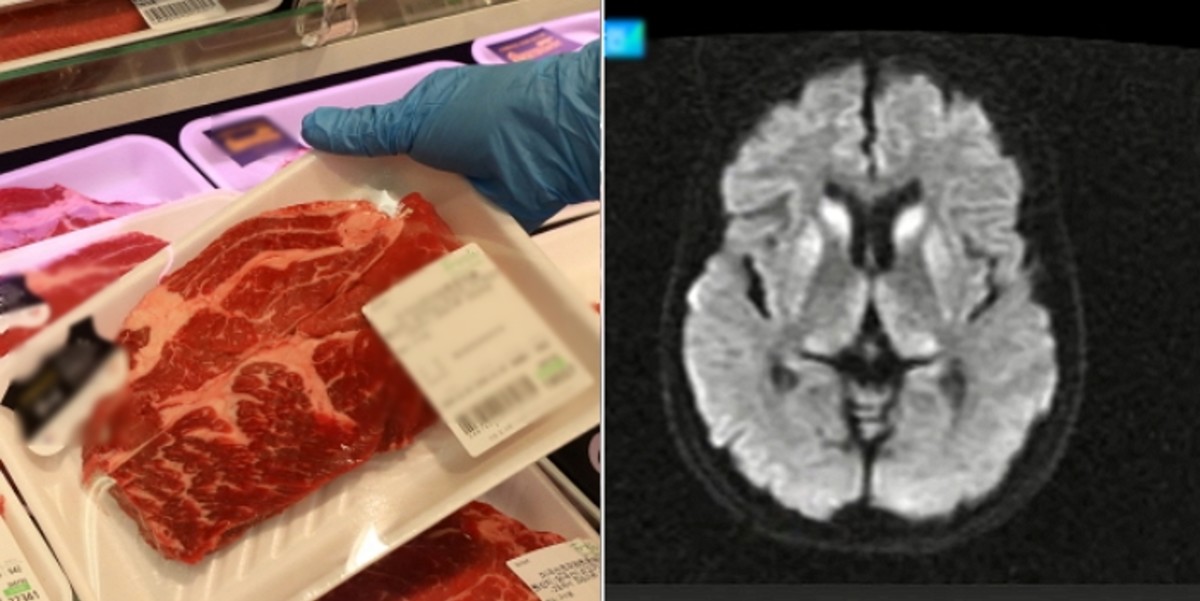

방역당국은 이번 사례가 '인간 광우병'으로 불리는 변종 CJD일 가능성을 조사하고 있다.

경기 북부에 사는 또 다른 20대 여성 역시 심한 치매 증상을 보여 CJD 의심환자로 등록됐다.

전문가들은 이번 CJD 의심 환자의 나이대에 주목했다. 주로 60대 이상에서 발병하는 것과 달리 20대라는 젊은 나이에 발병했기 때문이다. 최근에는 '인간 광우병'으로 불리는 변종 CJD는 모두 220여 건이 나왔는데 대부분 20대였다.

국내에선 20대가 CJD로 공식 진단받은 사례가 한 번도 없다. 변종 CJD는 별다른 치료법이 없어 증상이 나타난 뒤 빠르면 1년 이내에 사망하는 것으로 알려졌다.

질병청은 CJD는 물론 변종 가능성에 대해서도 조사하고 있다고 밝혔다. 또 빠르면 이번 주 중 전문가들로 구성된 사례판정위원회를 통해 이 여성들의 증상을 검토하기로 했다.